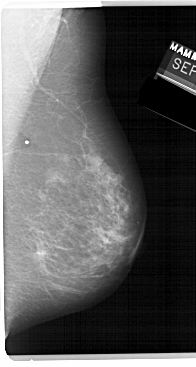

A_1224_1.RIGHT_CC

RIGHT_CC LINES 5386 PIXELS_PER_LINE 2671 BITS_PER_PIXEL 12 RESOLUTION 43.5 NON_OVERLAY